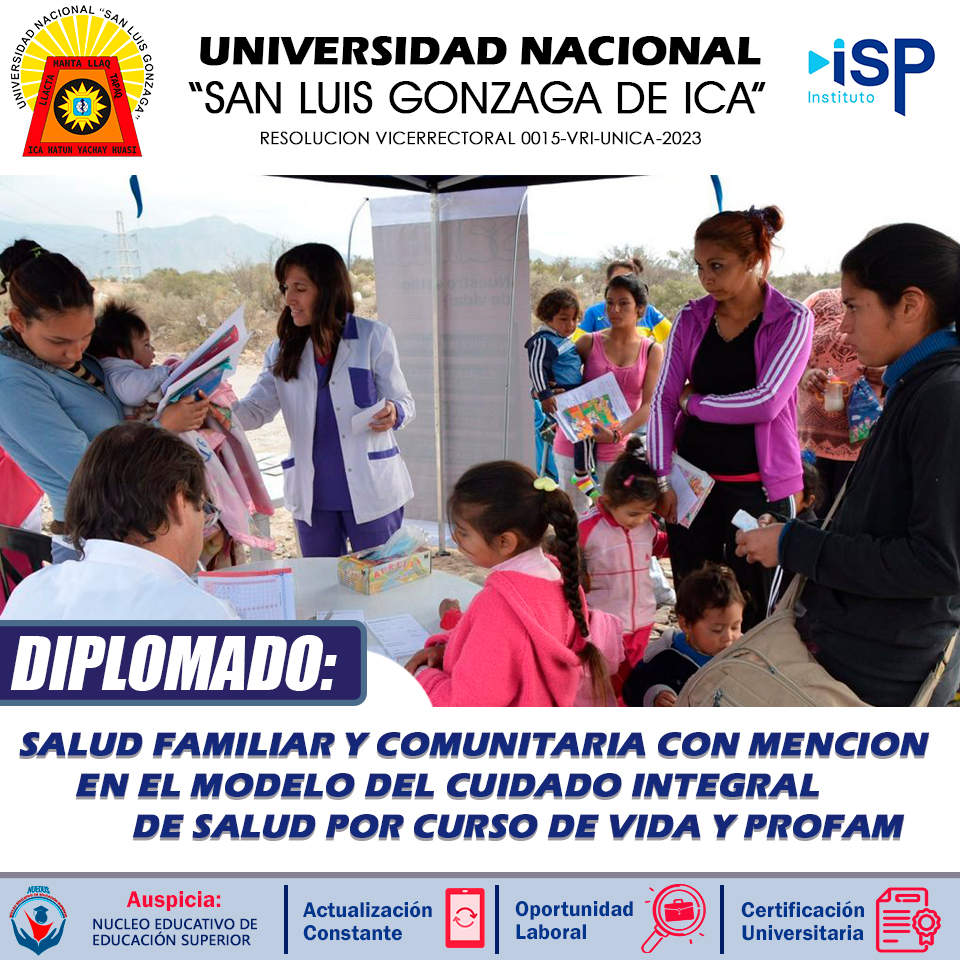

Especializados con nosotros.

Contamos con un equipo de docentes de Alto nivel.